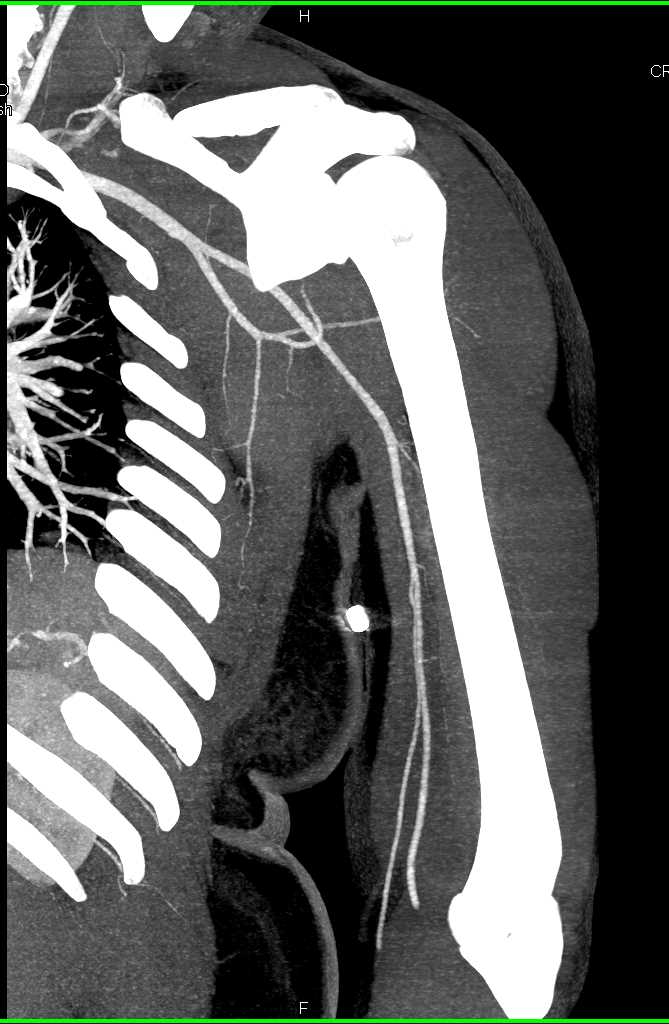

From www.researchgate.net

Computed tomographic angiography of chest showing a huge hematoma on Left Upper Chest Hematoma Icd 10 Nontraumatic hematoma of soft tissue. * brachial sheath hematoma [t14.8xxa] procedure (s): Extrapleural hematomas are uncommon and usually seen in the context of rib fracture, subclavian venous catheter traumatic insertion,. The 2025 edition of icd. Evacuation left upper extremity brachial sheath hematoma. Left Upper Chest Hematoma Icd 10.